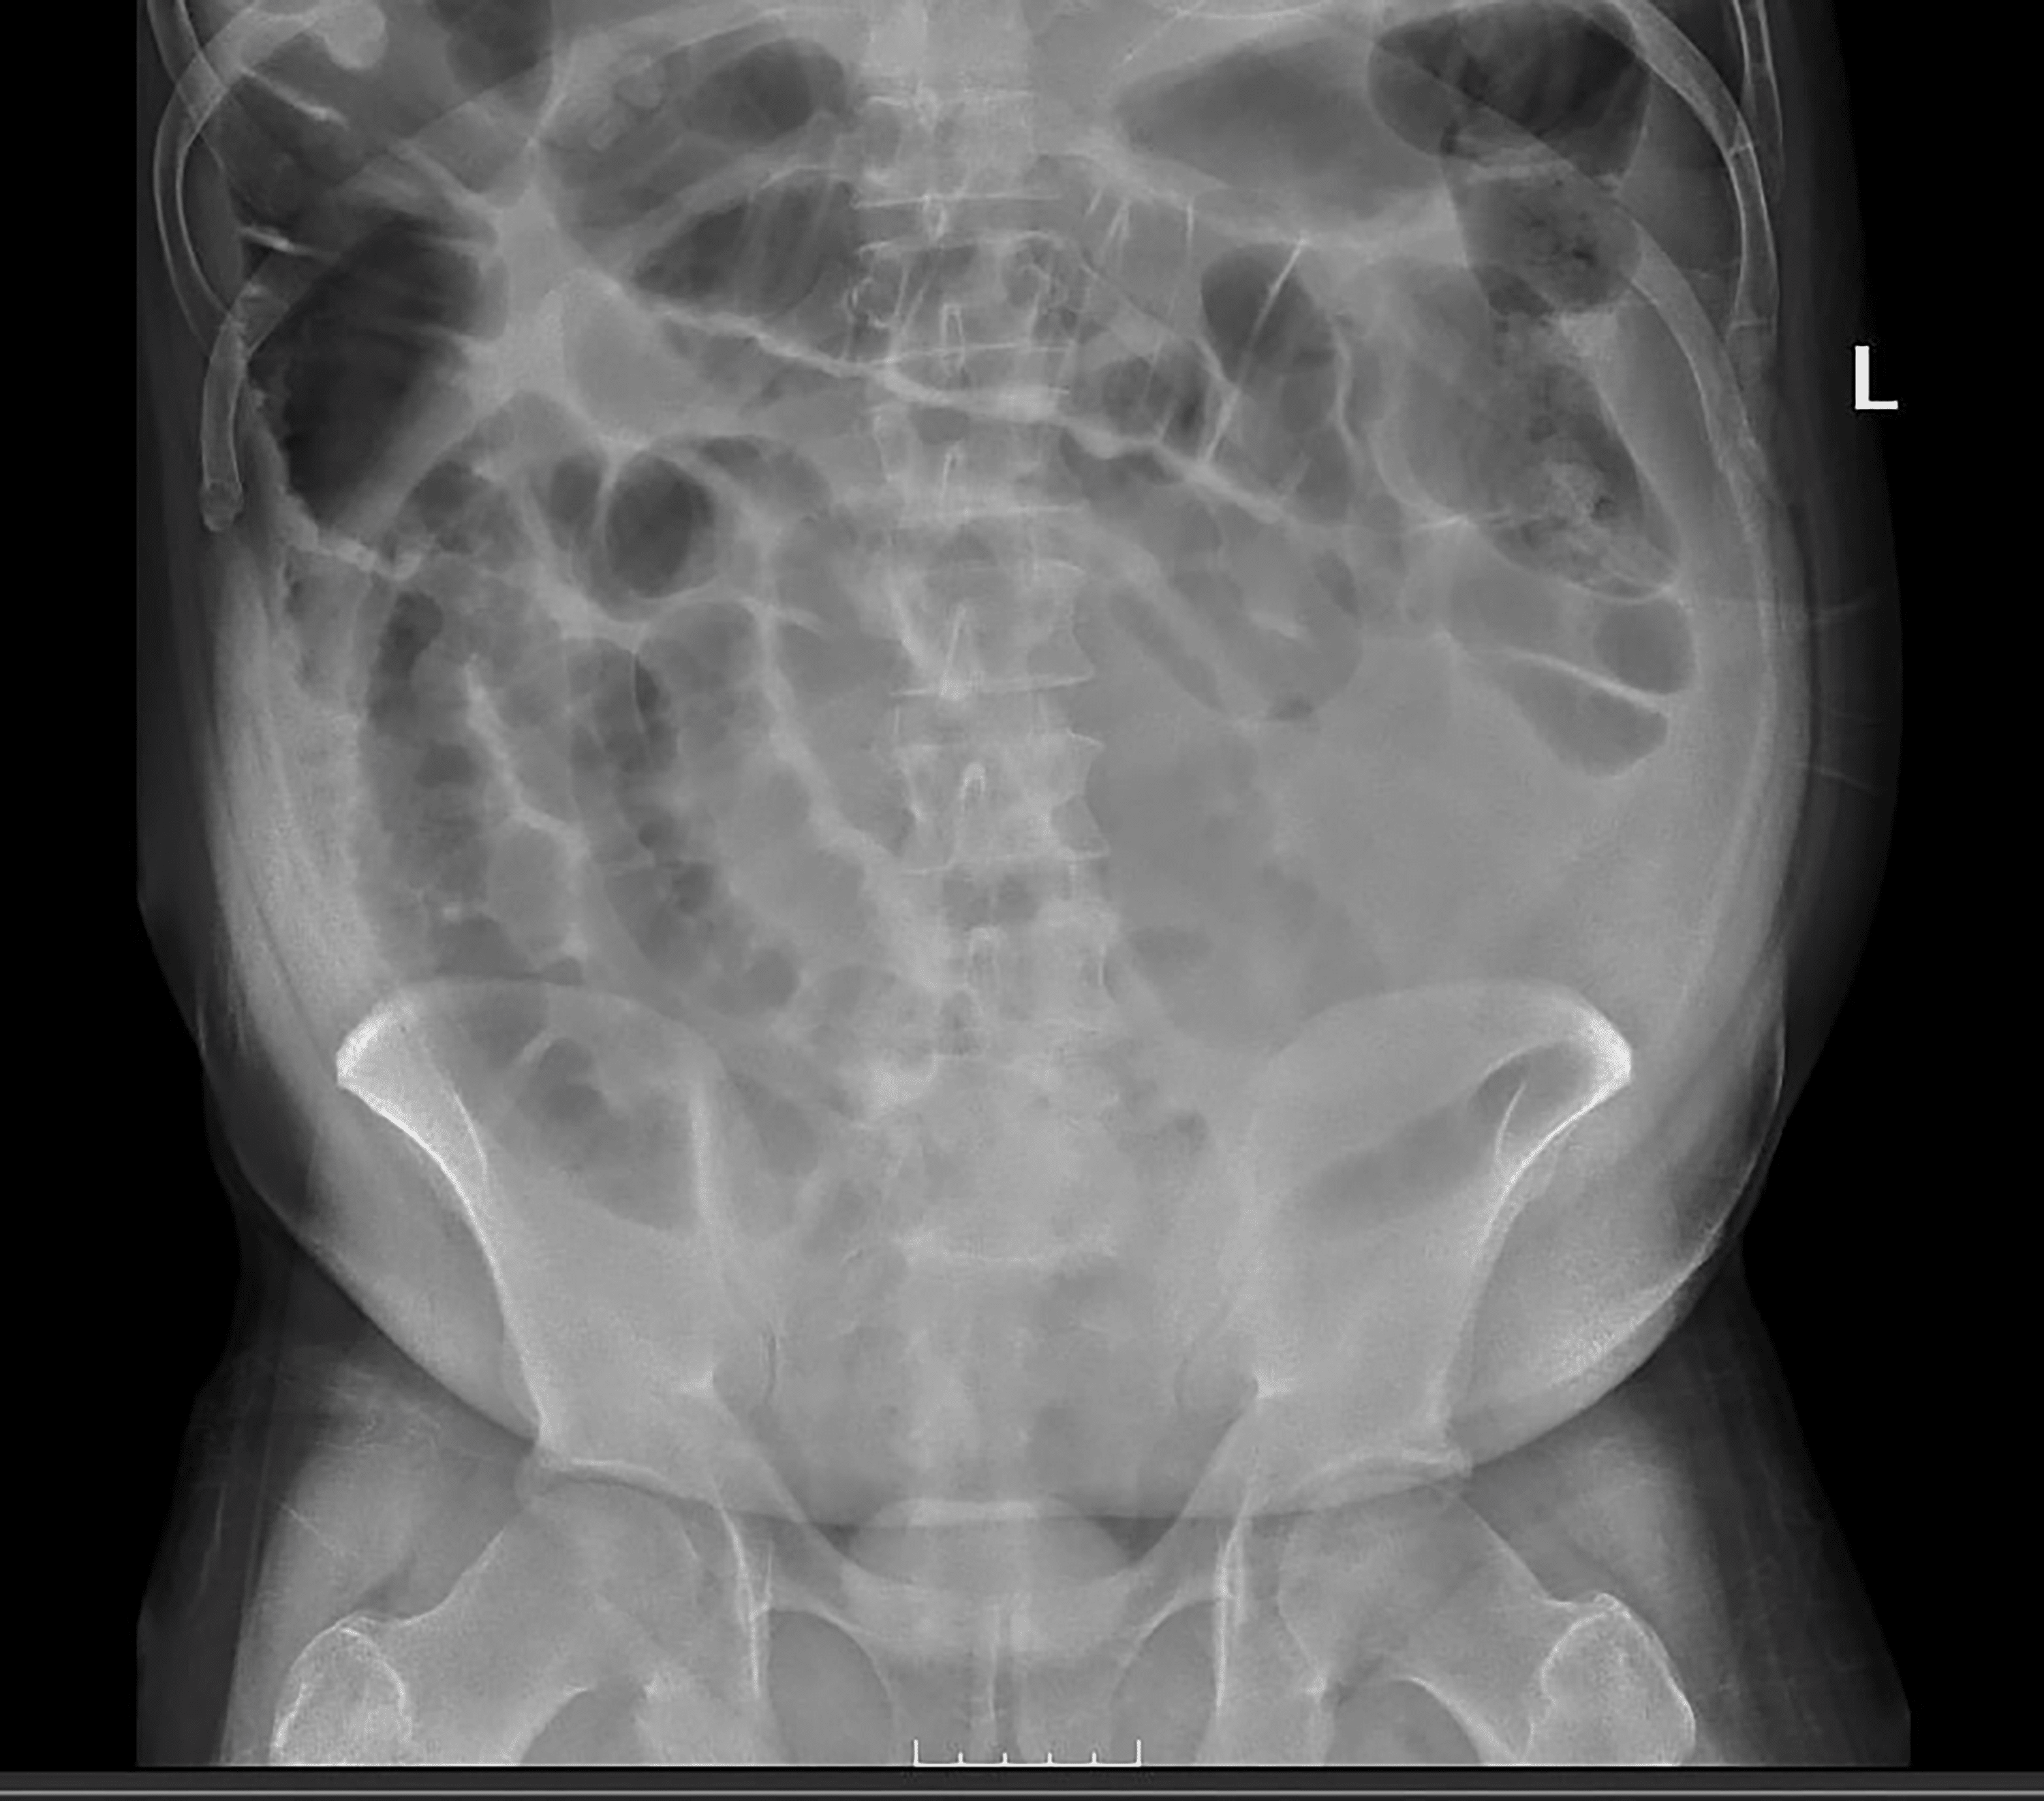

From www.wikidoc.org

Ischemic colitis abdominal x ray wikidoc Ischemic Colitis Perforation Ischemic colitis is a leading cause of acute abdomen in elderly patients. Gross and microscopic findings depend on the severity. Chronic forms usually present as chronic segmental colitis and may result in stricture formation. Ischemic colitis usually gets better on its own within 2 to 3 days. Ischaemic colitis occurs when there is an acute, transient compromise in blood flow,. Ischemic Colitis Perforation.